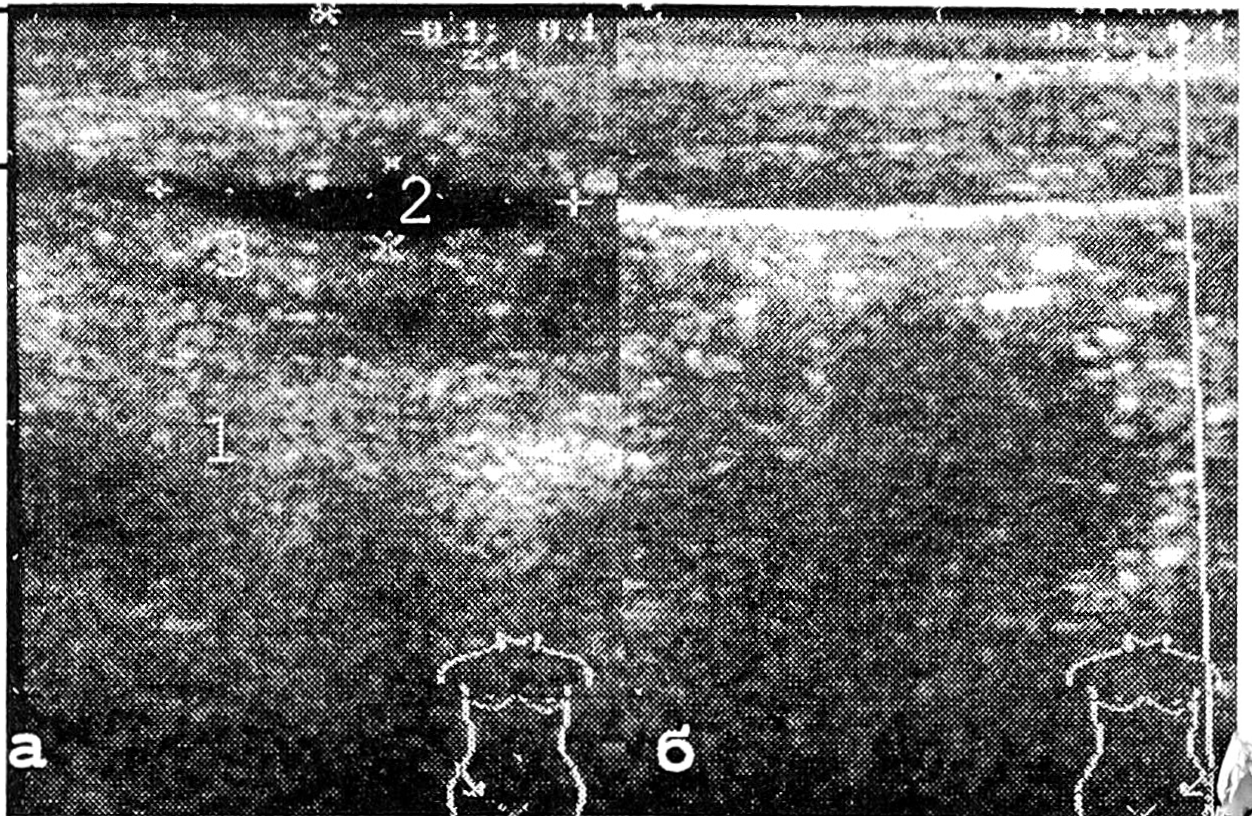

Достаточно информативным было УЗИ в мониторинге послеоперационной раны [1]. Так, отечность мягких тканей (послеоперационный рубец, место травмы) визуализировалась в виде утолщения кожи, увеличения объема и плотности подкожной жировой клетчатки по сравнению с интактной стороной. При выраженной отечности отмечалось истончение мышечных пучков (рис. 9).

Рис. 9. Эхограммы подвздошных областей передней брюшной стенки: а — справа (место оперативного вмешательства); б — слева (интактная сторона); 1 — кожа; 2 — подкожная жировая клетчатка; 3 — мышцы; ····· (1+2+3) — толщина мягких тканей.